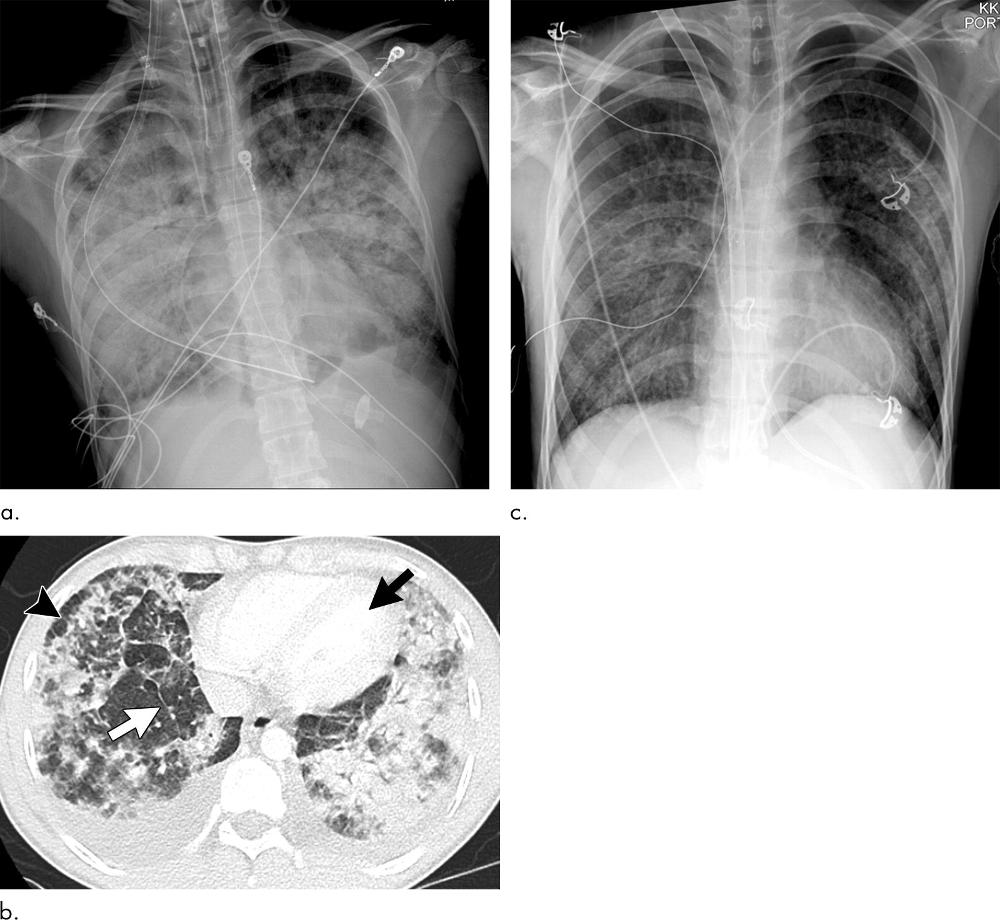

Figure 3. Images show electronic cigarette or vaping product use–associated lung injury with organizing pneumonia pattern secondary to vaping tetrahydrocannabinol in an 18-year-old man. (a) Posteroanterior radiograph shows midlung and lower lung consolidation and opacity bilaterally. Small right pleural effusion (black arrowhead) and septal thickening (white arrowhead) are seen. There is conspicuous sparing of cardiac borders (white arrows) as well as subpleural portions of lung (black arrows). (b) Coronal and (c) sagittal oblique images from CT nicely illustrate radiographic findings with mild and lower lung–predominant ground-glass opacity with few areas of consolidation. Prominent subpleural and perilobular sparing is present (black arrows). In addition, there is conspicuous sparing of peribronchovascular interstitium, best illustrated around larger pulmonary arteries and veins (white arrows). Hazy upper lobe–predominant ground-glass centrilobular nodules are present bilaterally (white arrowheads). In addition to thickening of interlobular septa, there are few areas with thickening of intralobular septa creating “crazy paving” pattern (black arrowheads). (d) Three days after initiation of steroids, patient showed dramatic clinical and radiographic improvement.

High-res (TIF) version